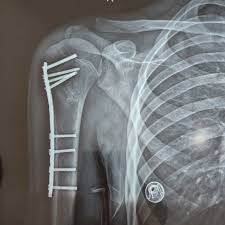

۲. درمان جراحی:

در صورت وجود جابجایی زیاد، چند تکه شدن شکستگی، یا اختلال در خونرسانی به سر استخوان بازو، جراحی پیشنهاد می شود: